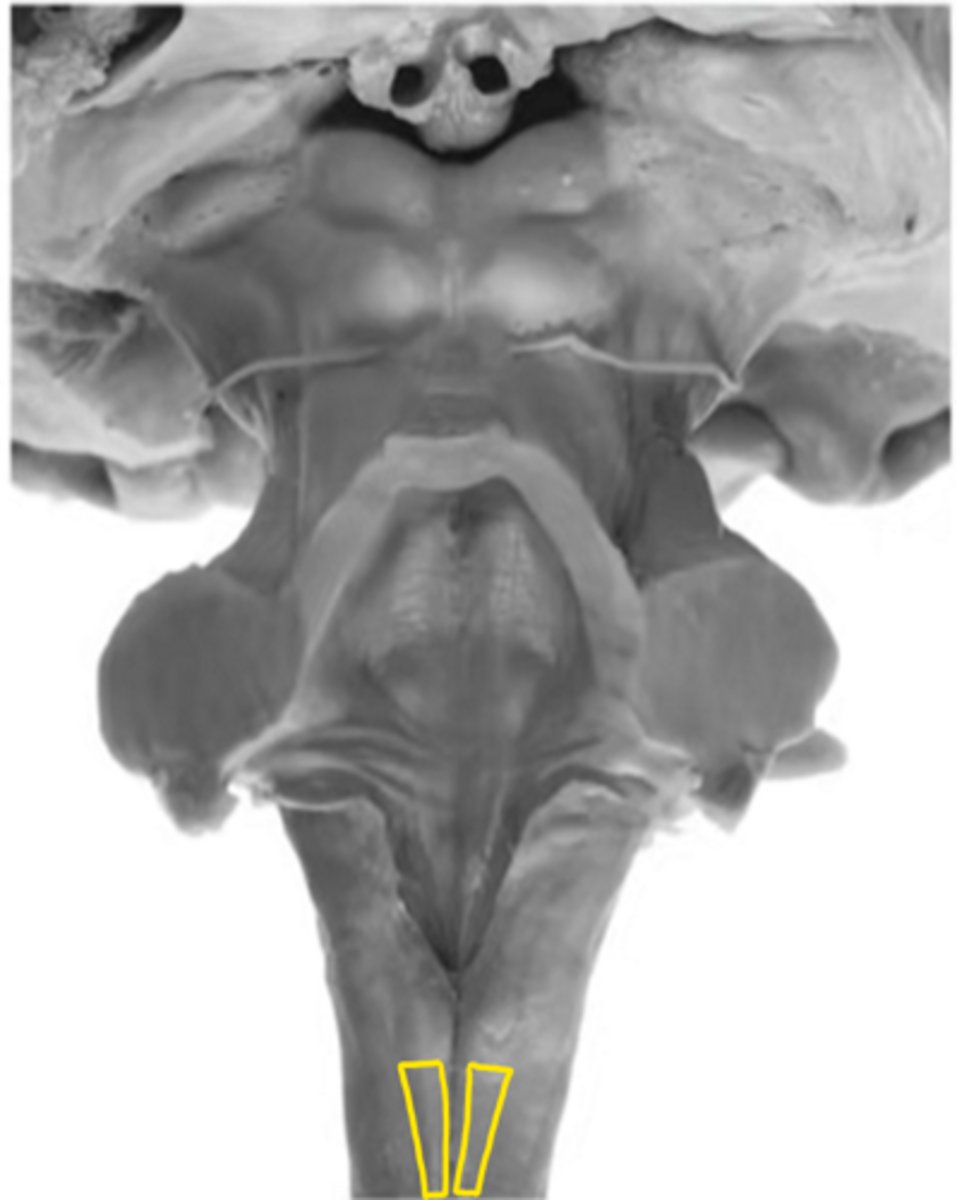

open medulla

ID the brainstem level